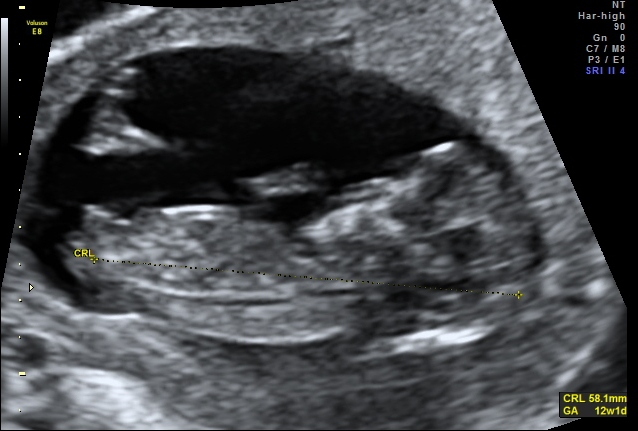

Well this little one has a very boy-ish head but I'm not sure what to make of the nub, if that's vene a nub captured in the images. Any guesses would be much appreciated.

I am gonna lean blue. The angle is not very much when you follow the spine curve, but it's got a bobble on the end that makes me think it might be rising. But it's a close call for me.

Baby looks slightly turned away so I wouldn't be surprised either way. My first thought was pink, though.

Pic 1 makes me think boy but Pic 2 looks pretty girly so I am saying 60/40 girl lean.

Thank you! Yes that's why I am so confused too. The two pics look quite different don't they. I wonder if perhaps something has been picked up in the first pic behind the nub, like part of the leg or perhaps?

In the second pic I think the nub looks girly, so I would lean pink. I wouldn't focus too much on skull shape because the head is a bit distorted in these images and also looks like head is turned sideways.